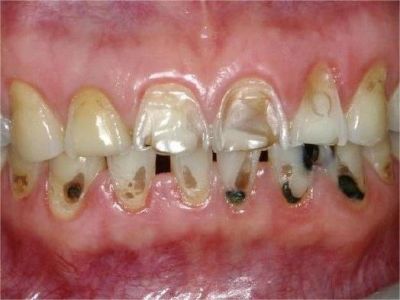

酸蚀症牙齿缺损严重有黑斑图

酸蚀症严重时会使牙齿出现大面积缺损,有三颗下牙损毁严重,露出不整齐的牙骨质边缘,几乎仅余留牙根。缺损处有黑斑,局部呈黄褐色,需积极就医进行牙齿修复。